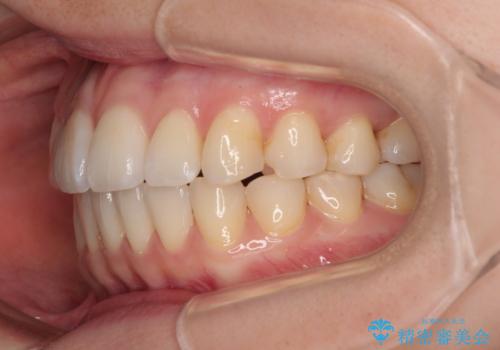

- 前歯のデコボコと、上下前歯が接触せずに前に飛び出していることを気にして来院された患者様です。

舌の突出癖が強く、それが原因で上顎歯列全体が前方に突出し、上下前歯が接触できない状態となっていました。

舌のトレーニングは不十分でしたが、1年半ほどで治療を終えることができました。

舌の突出癖が残っていると、容易に後戻りしてしまうため、トレーニングは継続するように指導しています。